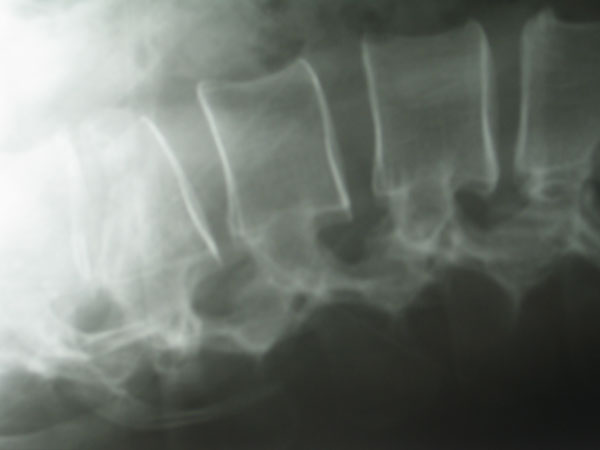

Bei der Kyphoplastie handelt es sich um eine Variante der Vertebroplastie. Genau wie bei der konventionellen Vertebroplastie werden unter Computertomographischer bzw. Röntgenbildwandlerkontrolle ohne Hautschnitt über einen minimalinvasiven Zugang zwei Kanülen transpedikulär (durch die Wirbelbogenwurzel, s.o.) eingebracht. Über die Kanülen werden zwei Arbeitskanülen eingebracht, über diese werden wiederum zwei mit Röntgenkontrastmittel „aufblasbare“ Ballons in den gebrochenen Wirbel eingeführt. Diese Ballons werden nunmehr unter Röntgenkontrolle und elektronischer Druckkontrolle vorsichtig aufgeblasen. Hierunter kommt es idealerweise zu einer nahezu vollständigen Wiederherstellung der ursprünglichen Wirblkörperkontur. Hiernach wird das Kontrastmittel aus den Ballons abgelassen, die zusammengefallenen Ballons können über die Arbeitskanüle entfernt werden. In den nunmehr im gebrochenen Wirbel gewonnenen Hohlraum wird dann über weitere spezielle Kanülen der vorbereitete Knochenzement ohne Druck eingespritzt.

Der Vorteil der Kyphoplastie besteht darin, daß der Knochenzement durch das Schaffen eines Hohlraumes ohne großen Druck eingespritzt werden kann, dieses soll bis zu einem gewissen Grad einen Zementaustritt aus dem Wirbelkörper z.B. in den Wirbelkanal verhindern. Anmerkend hierzu muß gesagt werden, das ein Zementaustritt aus dem Wirbel bedeutungslos ist, selbst das Eintreten von geringen Mengen Zement in den Wirbelkanal verläuft völlig asymptomatisch. Das Eintreten einer Zementembolie soll ebenfalls durch die geringe Druckaufwendung während des Einspritzprozesses vermindert werden. Mit der Kyphoplastie hat der Wirbelsäulenchirurg bis zu einem gewissen Grade die Möglichkeit, eine Wiederaufrichtung des gebrochenen Wirbels zu erreichen. Diese Möglichkeit ergibt sich bei der konventionellen Vertebroplastie nur sehr beschränkt, hier kann eventuell in Narkose bei frischen Frakturen durch entsprechende Lagerungsmöglichkeiten eine teilweise Wiederaufrichtung des Wirbels erreicht werden. Der Nachteil der Kyphoplastie ist in dem deutlich höheren Preis des Verfahrens zu sehen. Minimalinvasive Verfahren